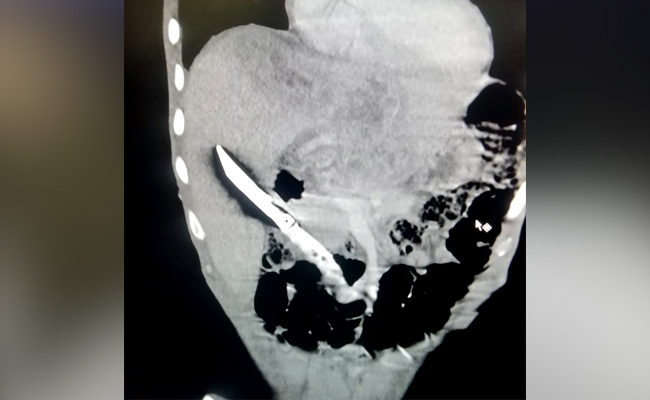

एम्स (AIIMS) के चिकित्सकों ने एक अनोखी सर्जरी को अंजाम दिया. एक युवक ने 20 सेंटीमीटर लंबा सब्जी काटने वाला चाकू निगल लिया था. डेढ महीने तक किसी को इसका पता तक नहीं लगा. जबकि चाकू लिवर में पूरा घंस गया था, वहां से आपरेशन कर चाकू निकालना बड़ी चुनौती का काम था.

नहीं मिला गांजा, तो चाकू निगल गया शख्स, X-Ray रिपोर्ट देख डॉक्टरों के उड़े होश, ऐसे निकाला बाहर